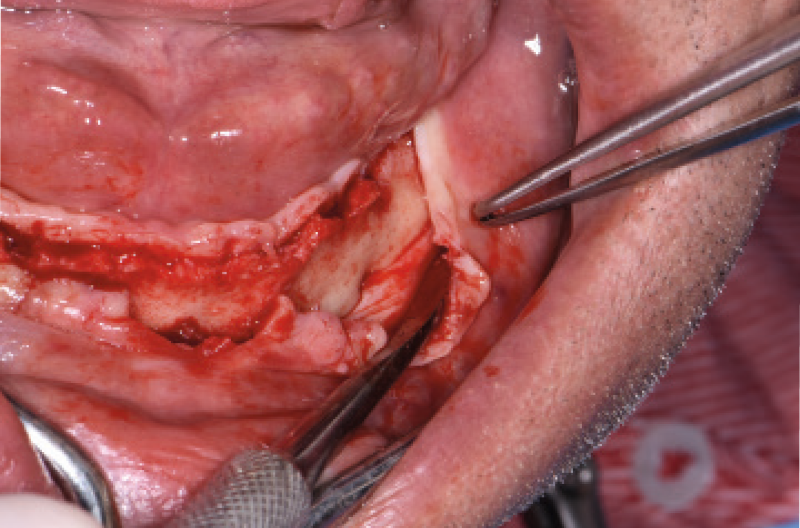

NellŌĆÖarcata inferiore ho posizionato distalmente 2 impianti Max Stability ├ś 3,75 mm L 12 e L 14 mm inclinati (ŌĆ£tiltatiŌĆØ) davanti ai forami mentonieri secondo il protocollo All-on-four, mentre nella zona sinfisaria ho inserito 2 impianti Narrow ├ś 2,9 L 12 mm (Figg. 15-20).

Fig. 16 – Esposizione del forame mentoniero di sinistra

Fig. 17 – Esposizione del forame mentoniero di destra